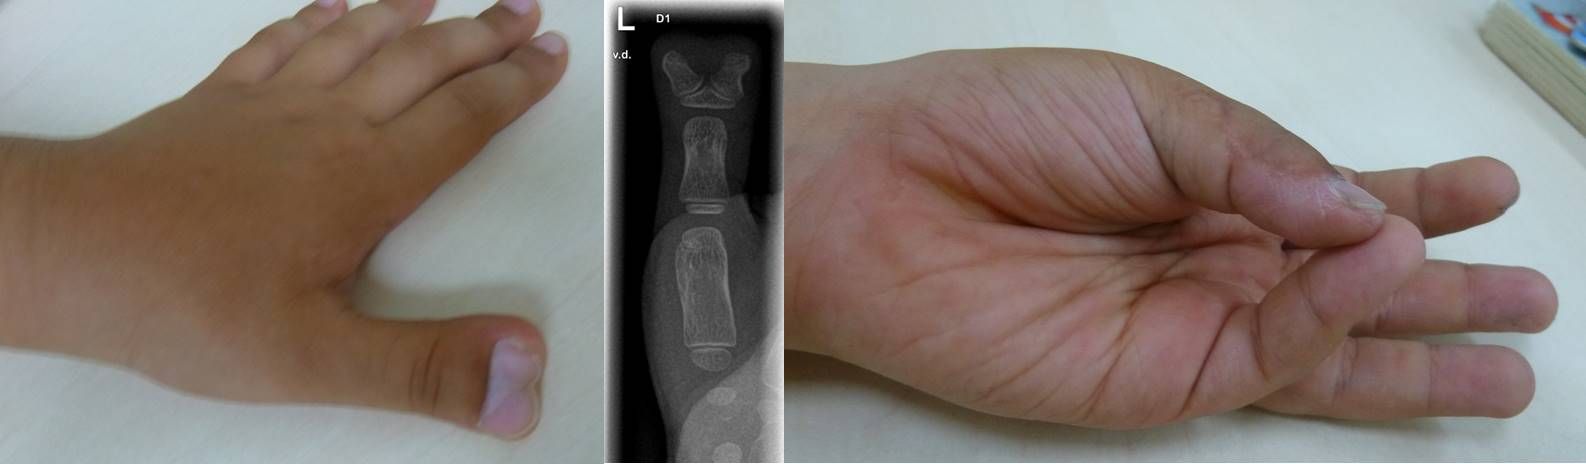

Bei der kompletten Doppelung ganzer Finger, erfolgt die operative Korrektur meist erst nach dem ersten Geburtstag. Das klinische Bild kann dabei, je nachdem, auf welcher Höhe sich der Daumen in zwei Anlagen aufteilt, sehr unterschiedlich sein. Die Korrektur besteht dabei nicht im einfachen Entfernen der überzähligen Anteile. Die oft anspruchsvolle Operation umfasst die Korrektur der meist zusätzlich bestehenden Verschmelzung von knöchernen gedoppelten Anteilen sowie die Stabilisierung des Bandapparates der betroffenen Gelenke und Verlagerung von Muskelansätzen des Daumenballens. In manchen Fällen muss auch eine Korrektur der knöchernen Achse erfolgen. Die Begrifflichkeit „Doppeldaumen“ ist hier manchmal irreführend, da es sich nicht um zwei normal entwickelte Daumen handelt sondern um Anteile eines Daumens, die sich auf zwei Anlage verteilen; somit ist der verbleibende Daumen fast nie so kräftig wie der gesunde Daumen der Gegenseite.